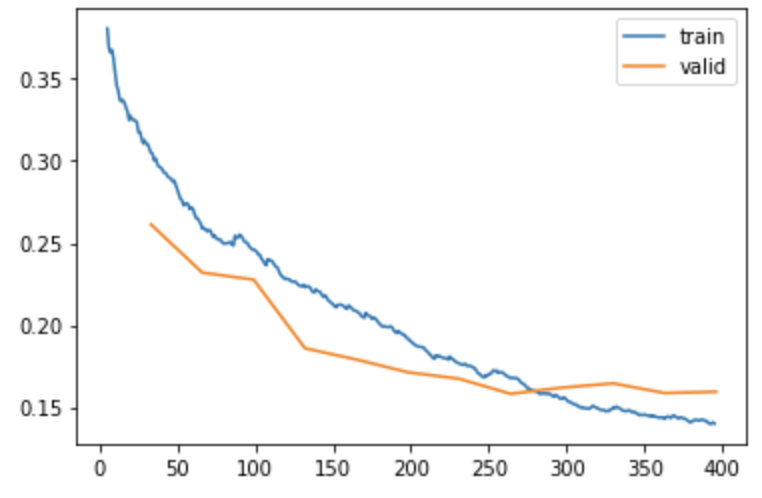

Fine tuning for 12 epochslearn.fine_tune(12, 1e-4)

epoch train_loss valid_loss dice jaccard_coeff time

0 0.582160 0.433768 0.593044 0.421508 00:38

epoch train_loss valid_loss dice jaccard_coeff time

0 0.307588 0.261374 0.712569 0.553481 00:38

1 0.261775 0.232007 0.714458 0.555764 00:38

2 0.246054 0.227708 0.781048 0.640754 00:38

3 0.224612 0.185920 0.796701 0.662097 00:39

4 0.208768 0.179064 0.821945 0.697714 00:39

5 0.192531 0.171336 0.816464 0.689851 00:39

6 0.177166 0.167357 0.820771 0.696023 00:39

7 0.168222 0.158182 0.838388 0.721745 00:39

8 0.155157 0.161950 0.829525 0.708709 00:39

9 0.148792 0.164533 0.828383 0.707043 00:38

10 0.143541 0.158669 0.833519 0.714559 00:39

11 0.140083 0.159437 0.832745 0.713422 00:38